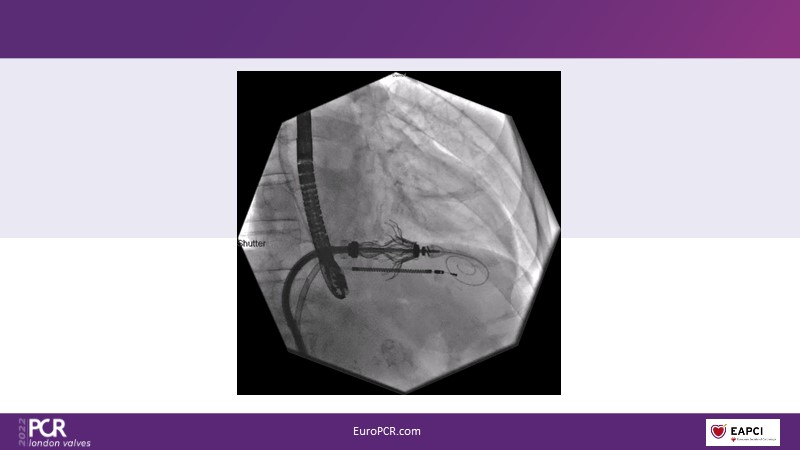

In this session from PCR London Valves 2022, discover the new Venus MedTech technology for tricuspid and pulmonary valve replacement, and a review of the clinical indications, selection criteria and procedural details.

- To learn about Venus MedTech technology, clinical indications and procedural details of valve replacement systems

- To learn more about the clinical experience and outcomes with Cardiovalve tricuspid and Venus P-valve